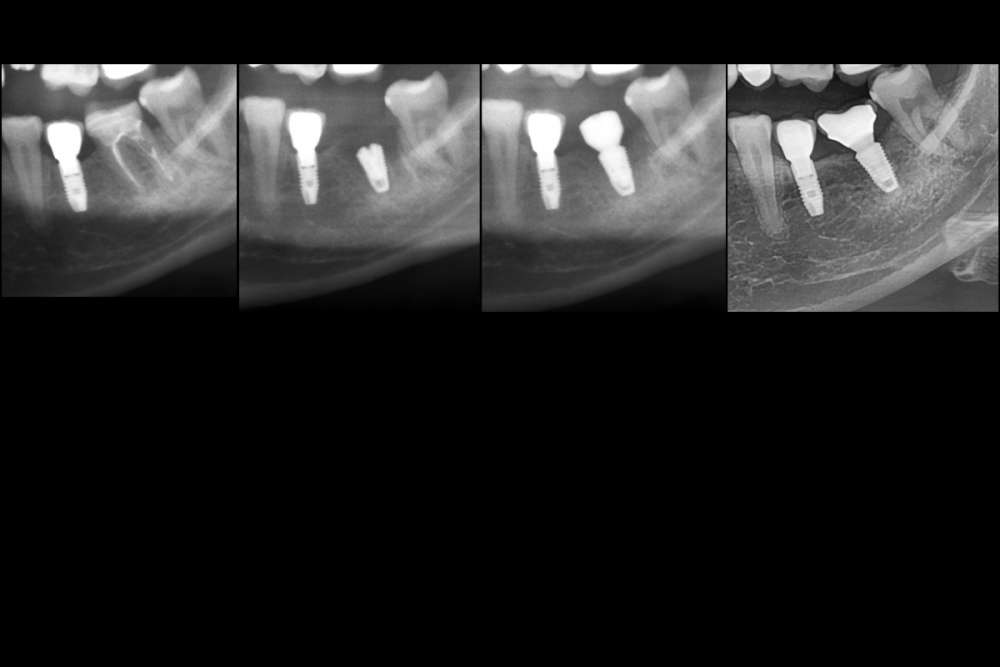

Карен Аванесов Опубликовано 21 февраля, 2022 Автор Поделиться Опубликовано 21 февраля, 2022 Дозрела костна ткань. Возвращаясь к вопросу о "волшебстве" брендовых систем.... Безусловно, молодому специалисту, через сопливый нос бубнить на консультации что от СТАВИТ страуманн, мобель или аштру, поднимает самомнение, окрыляет, иногда и до звездной болезни, помогает быстрее "заматереть,"но сути не меняет. Кость "подрастает" не только аштре например, что иногда демонстрируют с восторгом, но и на отстойном дентиуме тоже, и думаю и на отстойной альфа-био и т.д., т.е. все-же от условий зависит, пациента и конечно техника, что там как и дальше будет. Соберу кейс покажу вошебный рост на голых витках корейского народного ширпотреба)))) 1 Ссылка на комментарий